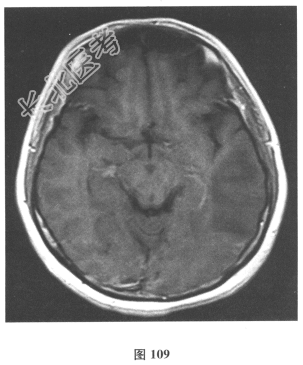

脑脊液检查:常规、生化均正常,CSF-病毒TORCH(-),抗Hu、Yo、Ri均阴性,OB、MBP正常。血清抗Hu、Yo、Ri均阴性。颅脑MRI显示左颞枕、右顶枕多发长T₁、长T₂信号,Flair高信号,病变累及皮质及皮质下白质,病灶无强化,见图108~图114。)根据颅脑MRI,需要鉴别的疾病应是